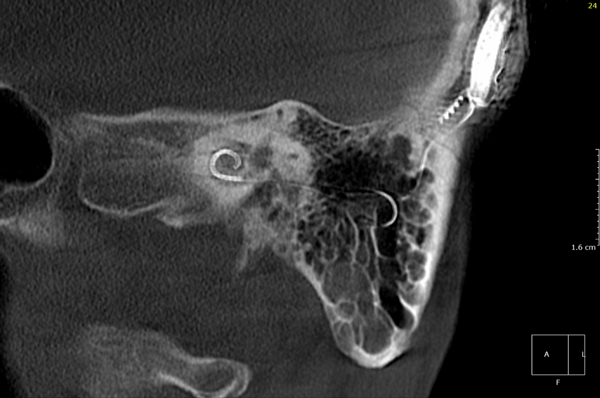

Both patients were imaged immediately with CBCT using SCANORA® 3Dx (Soredex, Tuusula, Finland). The field of view (FOV) was 140 x 165 mm and voxel size 0.2 mm. Imaging parameters were 90 kV, 8 mA, 4.00s. Standard 1 mm axial, coronal and sagittal reformations were made, as well as MIP and 3D reconstructions using OnDemand3D™ software (Cybermed, Seoul, South Korea).

CBCT proved to be optimal for imaging of these implants because of the superior bony delineation and nearly artefact free images. All four parts, i.e. the receiver stimulation part, extracochlear electrode implanted on the surface of the temporal bone, the extracochlear electrode plate and the intracochlear electrode array could be well imaged with CBCT.

On CBCT all four of the important parts of the implant were very well seen both on the axial slices and three dimensional surface reconstruction images. The implant is placed on magnetic plates, and the extracochlear part was seen in an abnormal separated position. The intracochlear electrode array showed no signs of separation in either of the cases. The intracochlear electrodes were well seen in both of the cases.

Figure 1: Patient 1 - Sagittal oblique reformatted CBCT image showing the intracochlear portion of the implant.